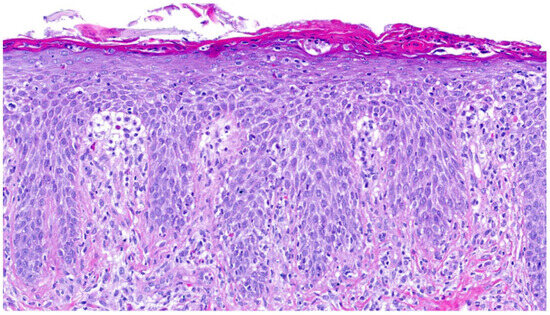

Inflammatory skin diseases are characterized by complex interactions between immune pathways, epidermal barrier function, and environmental triggers, leading to distinct clinical and histopathological features. This narrative review aims to integrate current knowledge on the cutaneous immune microenvironment across major inflammatory skin diseases, including

Inflammatory skin diseases are characterized by complex interactions between immune pathways, epidermal barrier function, and environmental triggers, leading to distinct clinical and histopathological features. This narrative review aims to integrate current knowledge on the cutaneous immune microenvironment across major inflammatory skin diseases, including atopic dermatitis, psoriasis, hidradenitis suppurativa, and vitiligo. A comprehensive literature search was conducted using PubMed, Web of Science, and Scopus, focusing on studies published between 2021 and early 2026. The findings highlight disease-specific immune signatures, such as Th2-driven inflammation in atopic dermatitis, IL-23/Th17 axis activation in psoriasis, neutrophil-dominated responses in hidradenitis suppurativa, and cytotoxic T-cell-mediated melanocyte destruction in vitiligo. These molecular pathways are closely reflected in histopathological patterns, emphasizing the link between morphology and immunopathogenesis. Advances in targeted therapies, including biologics and Janus kinase inhibitors, demonstrate the clinical relevance of these pathways and support a transition toward mechanism-based treatment strategies. Dermatopathology is increasingly contributing to precision medicine approaches by supporting correlations between tissue features, immune pathways, and potential therapeutic targets. This review provides a framework for improved disease stratification and for the development of personalized treatment strategies in inflammatory skin diseases.